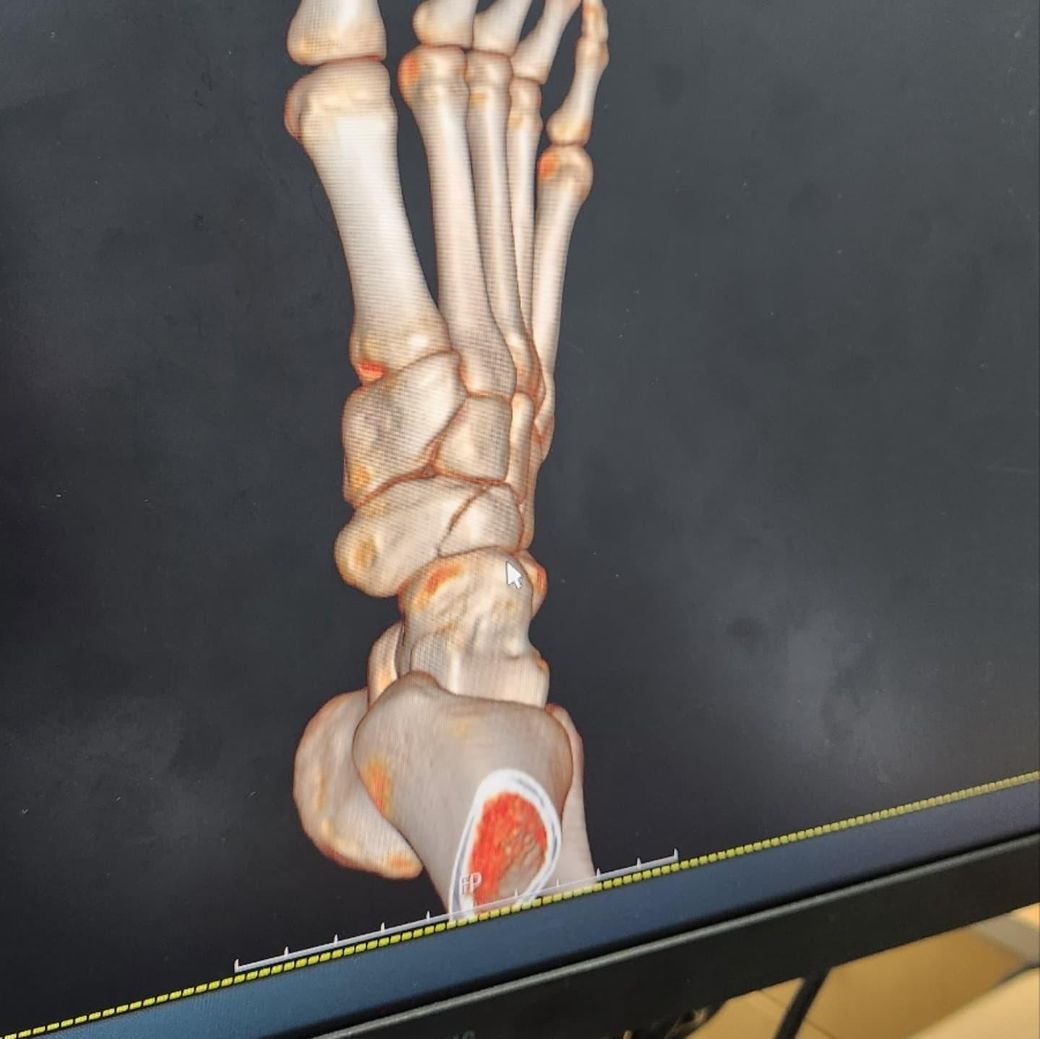

족부 주상골 골절 발바닥에 피 뭉쳐있는 느낌

비수술 통깁스 입니다 어제부터 발바닥에 엄청 따뜻한 피가 모여있는 느낌인데 지들끼리 모여있다가 발을 내리면 아래로 내려가요 혹시 피가 고여있는 걸까요? 안좋은 건가요...? 참고로 10월 6일에 골절됐습니다. 아래 엑스레이는 10월 6일 촬영 사진입니다.발바닥이 엄청 따뜻해요...열감이랑은 다른느낌으로...끈적한 액체가 들어있는 느낌

• 1번 째 사진

• 2번 째 사진